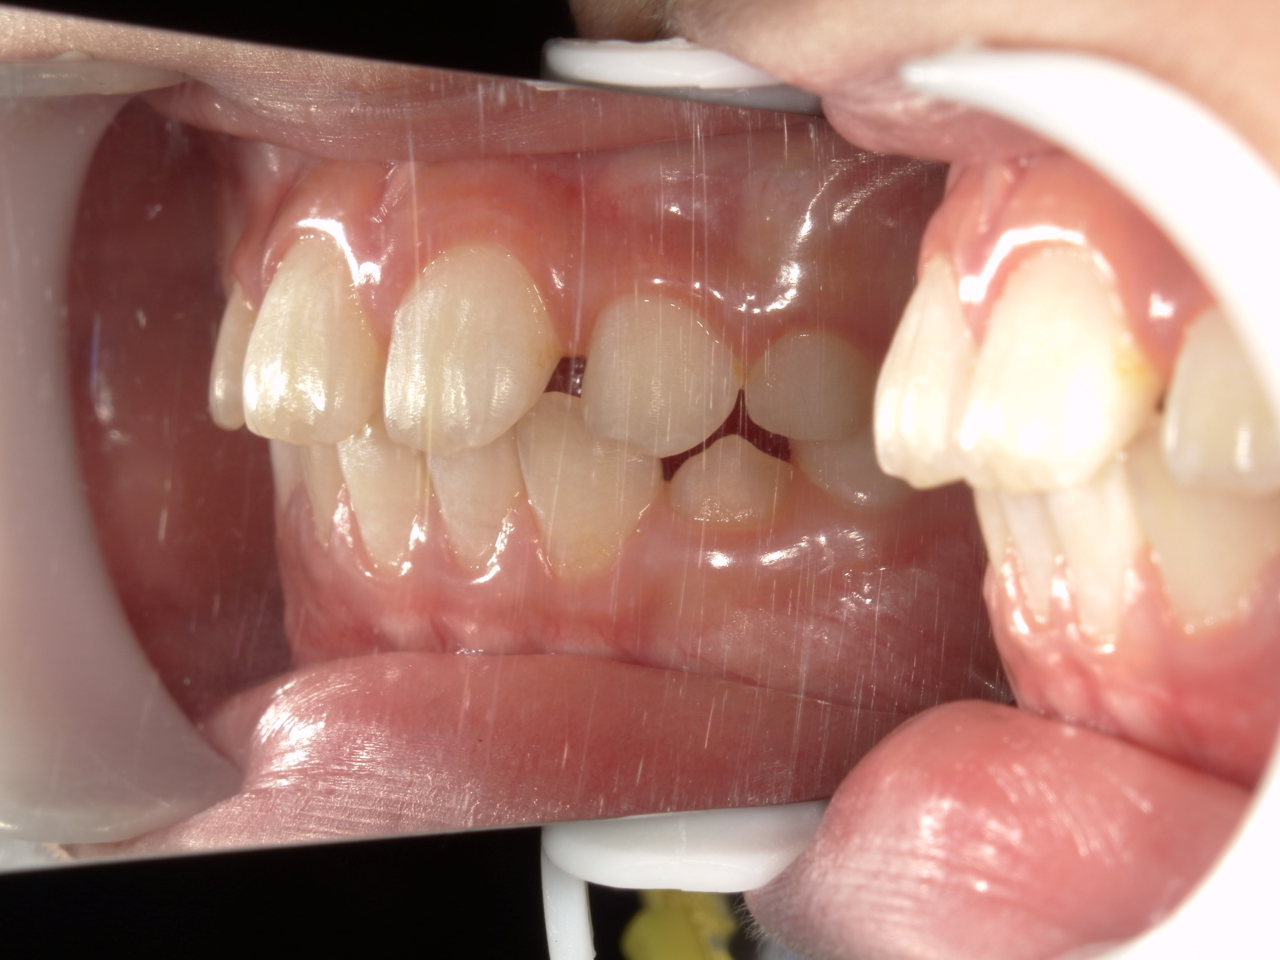

治療前

治療説明 歯科矯正で取り外し可能な矯正方法である床矯正で治療しました

治療期間 2年1か月

治療費200000 円

治療後

治療の副作用(リスク)歯の動き方には個人差があり、予想された治療期間が延長する可能性があります。。床矯正の使用状況、矯正歯科治療には患者さんの協力が必要であり、それらが治療結果や治療期間に影響します。2次矯正が必要になる場合もあります。